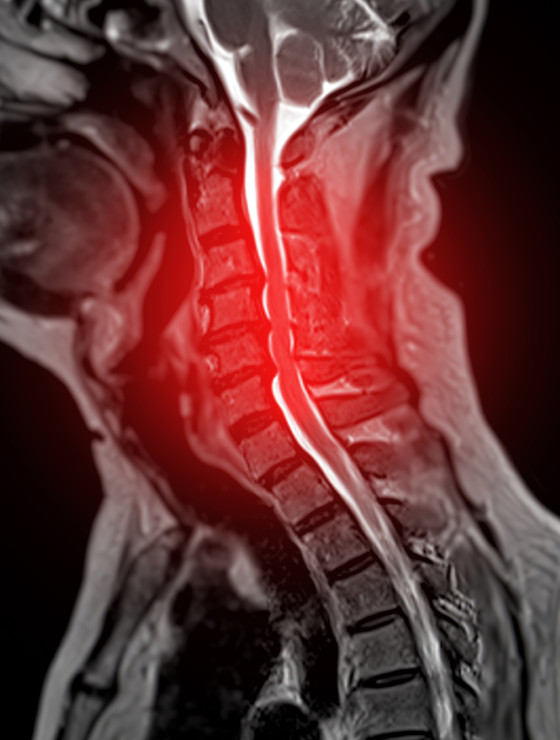

CIRURGIA ENDOSCÓCOPICA<br />

DA COLUNA

Inovação e tratamento da hérnia de disco

Dr. Fernando Soccol é médico ortopedista referência em cirurgia da coluna vertebral, com mais de uma década de experiência, expoente na área de cirurgia minimamente invasiva e cirurgia endoscópica da coluna.

Cirurgias na coluna são seguras e previsíveis. Ao longo das últimas décadas observou-se refinamento das técnicas operatórias e dos equipamentos de projeção de imagens, como microscópios e vídeo-endoscópios. Hoje é possível “navegar” em cirurgias guiadas por tomografia tridimensional, além de monitorar a atividade neurológica do paciente em tempo real.